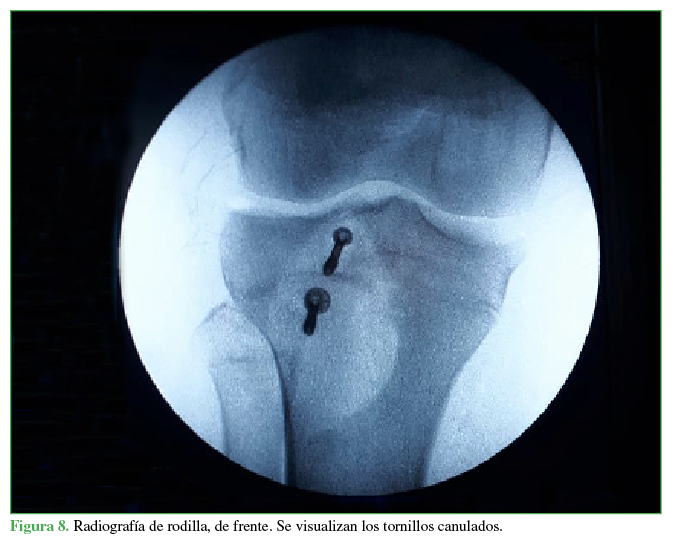

La cirugía consistió en una reducción abierta más osteosíntesis con colocación de dos tornillos paralelos sin afectar la fisis (uno en la región de la metáfisis y otro en la región de la epífisis). Durante la operación, se constató la lesión del tendón rotuliano con invaginación de las fibras distales en el foco fracturario, se continuó con su liberación y se realizó una sutura a nivel del periostio, en la región anterior de la tibia proximal (Figuras 4 y 5), se procedió a la reducción y osteosíntesis con dos tornillos paralelos de 3,5 mm y la colocación de arandela, ubicados en la epífisis y la metáfisis (Figuras 6,7,8). Se le colocó un yeso cruropedio en extensión sin carga por seis semanas para luego continuar con el tratamiento de rehabilitación (Figura 9).

El tipo de material que utilizamos al igual que otros autores (Balmat y cols.)10 son dos tornillos canulados con rosca incompleta más arandela, colocados en paralelo, uno en la epífisis y otro en la metáfisis salteando la fisis, explorando previamente el trazo fracturario por presentar interposición del tendón rotuliano sin la colocación de cerclaje, a diferencia de Nikiforidis y cols. que utilizan ese método de cerclaje, rehabilitación precoz sin inmovilización y marcha sin carga asistida con muletas hasta la sexta semana para continuar con el retiro del cerclaje en la octava semana, y necesitan un segundo tiempo quirúrgico para el retiro del material, lo que demora el retorno al deporte y provoca casos con atrofia de cuádriceps. También tenemos diferencias con Pesl y Havranek, quienes realizan una primera fijación interna con colocación de tornillos percutáneos como primer intento obviando la exploración tendinosa; en este caso, el tiempo de inmovilización, la carga completa y el retorno a la actividad deportiva fueron más rápidos, iguales a los descritos por Agrelo y cols., y Casas-López y cols. En nuestro caso, no fue posible realizar una resonancia magnética como sugieren Tuca y Pineda11 por no disponer de un resonador y porque el paciente no tuvo síntomas meniscales en los controles clínicos.